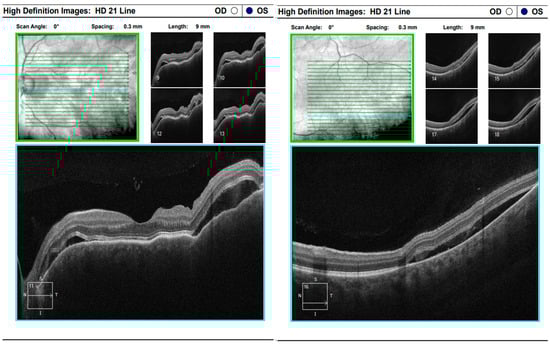

At the scheduled follow-up, although the periocular inflammation had improved, the patient reported markedly blurred vision in the left eye, with BCVA measured at 0.9 and subjective metamorphopsia on the Amsler grid. Biomicroscopy revealed pronounced anisocoria, with the left pupil wider than the right but still reactive to light. Fundoscopic examination was unremarkable in the right eye, while the left eye demonstrated macular edema. Optical coherence tomography (Zeiss Cirrus 5000) confirmed macular edema with isolated cystoid spaces and no evidence of optic disk swelling (Figure 13 and Figure 14). B-scan ultrasonography revealed bilateral scleral thickening, prompting revision of the working diagnosis to probable bilateral scleritis, likely of autoimmune origin. Parabulbar administration of Dexamethasone was performed, resulting in improvement of both subjective symptoms and objective findings.

Figure 13. Analysis protocol “HD 21 Line” of the right and left eye.